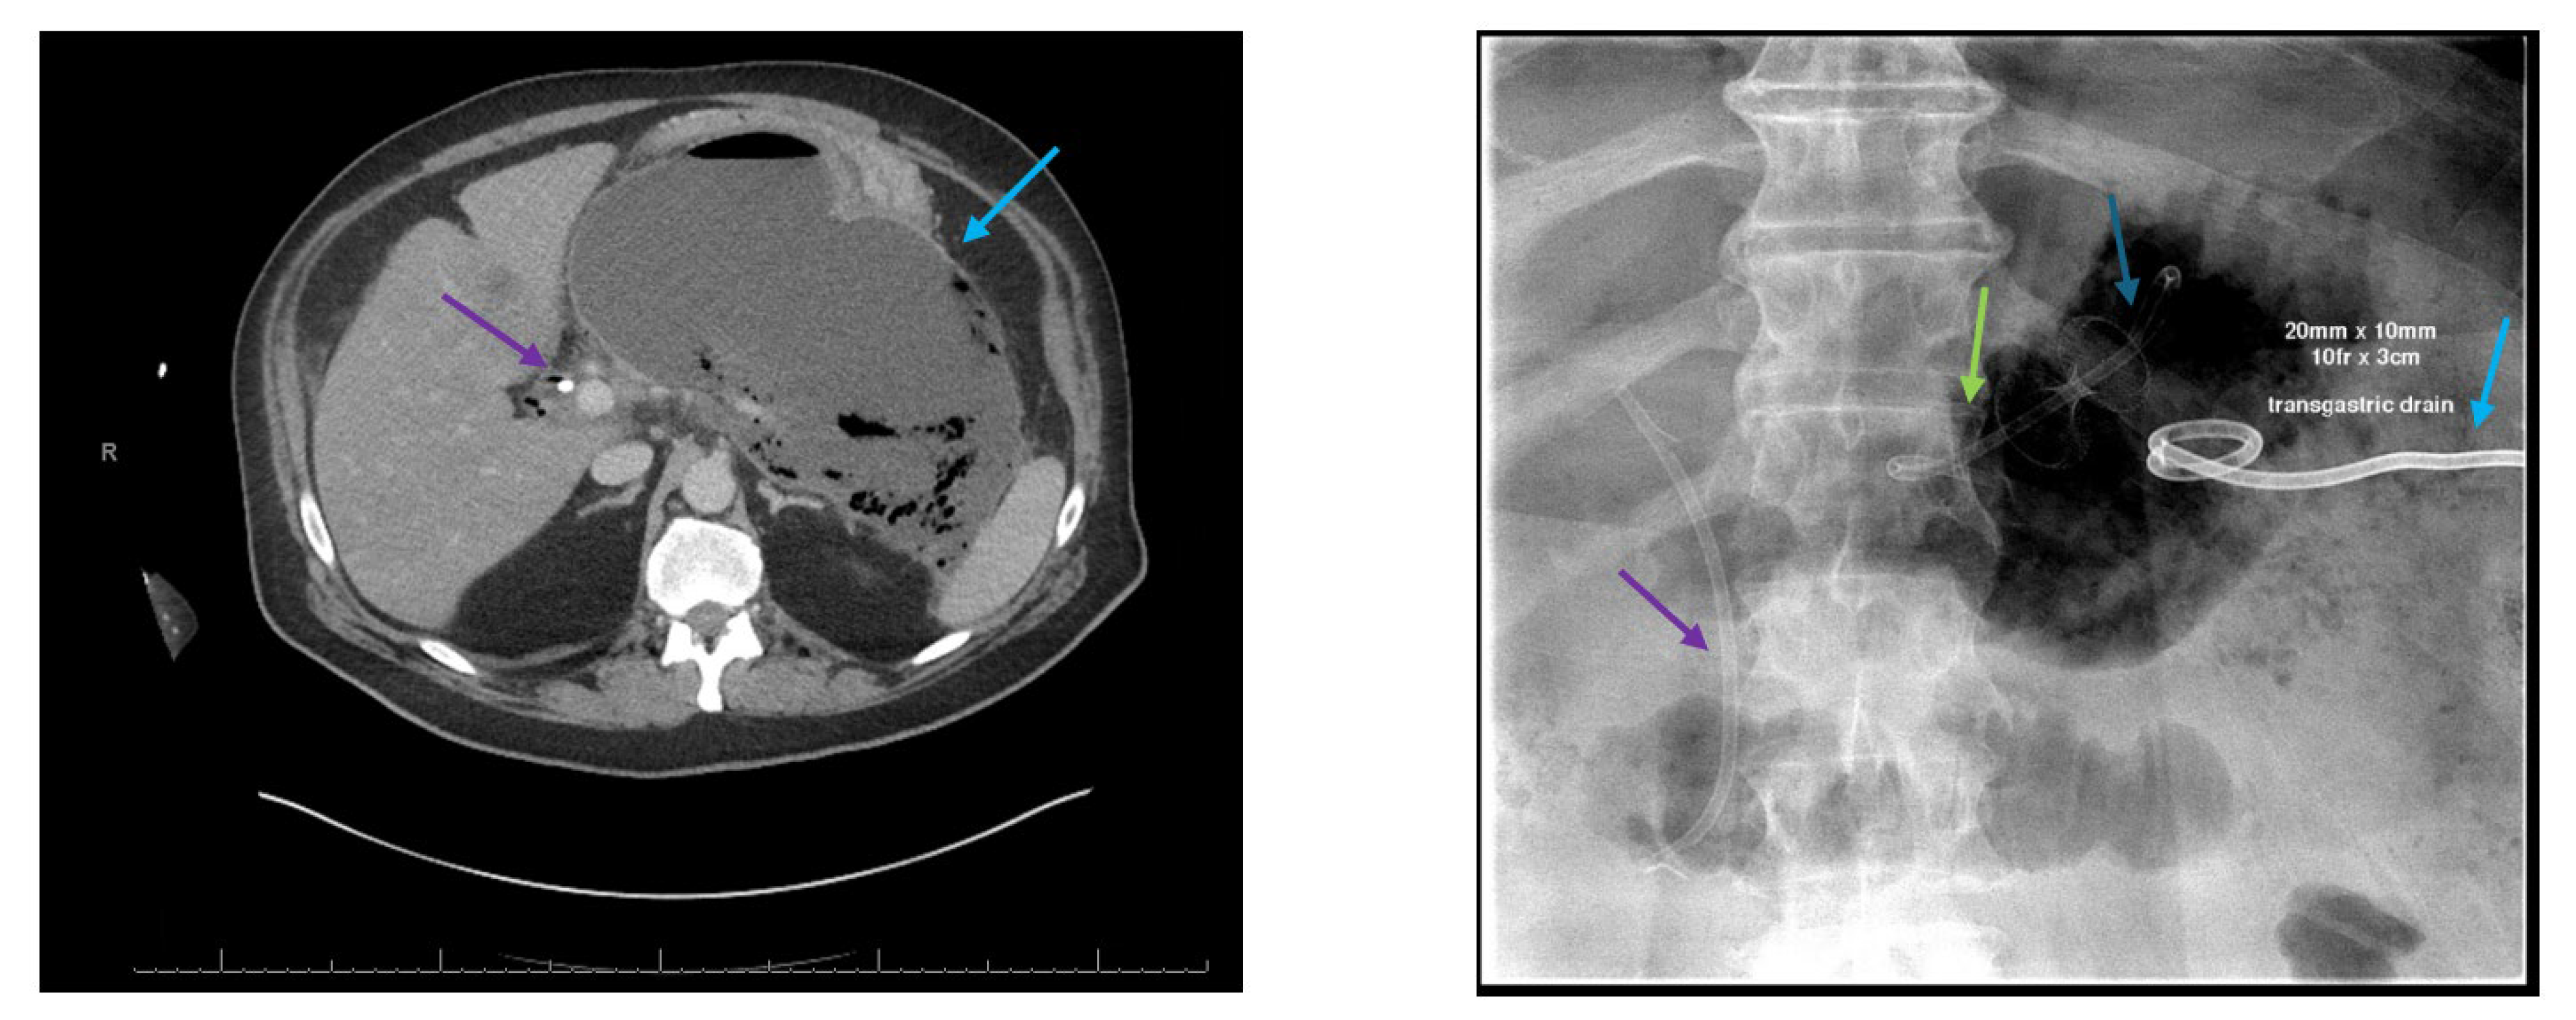

2.6. Dual Modality Drainage

2.8. Pancreatic Fistula Treatment

2.9. Approach to Disconnected Pancreatic Duct Syndrome (DPDS) After Severe Pancreatitis